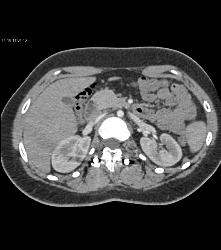

Small Caliber Aorta With Hardware Screw Abutting Aorta